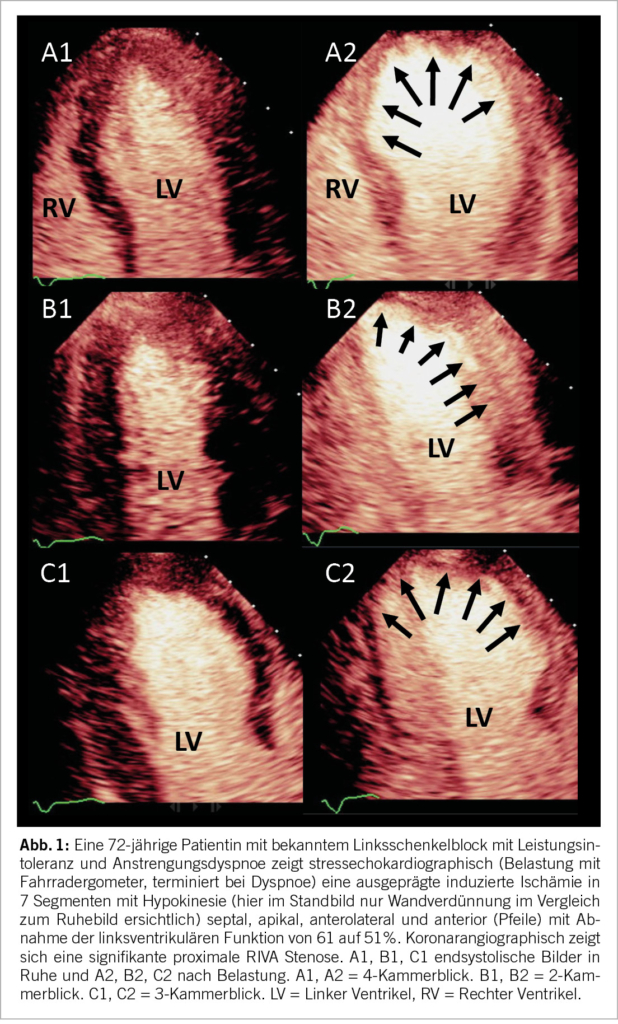

Weitere Gründe für die Durchführung eines funktionellen Ischämietests ergeben sich, wenn bereits eine koronare Herzerkrankung bekannt ist und Fragen zur Progression, höheren Kalkablagerungen oder moderaten Koronarstenosen bestehen, die mittels Koronar-CT diagnostiziert wurden. Das Ausmaß der myokardialen Ischämie beeinflusst die weiteren Schritte in Bezug auf Diagnose und Therapie. Eine prognostisch relevante Ischämie liegt vor, wenn drei oder mehr Segmente mit belastungsinduzierter Hypokinesie oder Akinesie auftreten (Abb. 1).